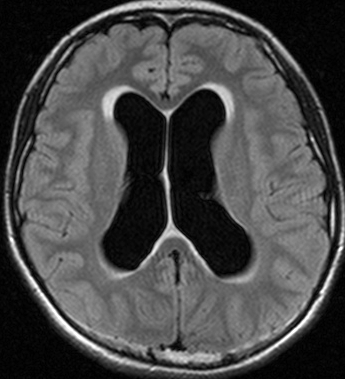

思春期の女の子にできた小脳腫瘍です。とても大きく見えますがほとんどが水たまり(のう胞といいます)。第4脳室が腫瘍で圧迫されて閉塞性水頭症になりました。のう胞の中に出血がありますが毛様細胞性星細胞腫では腫瘍内出血をしばしば見ます。右の写真で脳室が大きくなっています。こんなに大きいのに小脳症状は全くなくて,頭痛と嘔吐が症状でした。

手術後のMRIです。水頭症も改善してますから症状も消失しましたし,すぐに退院です o(^o^)o